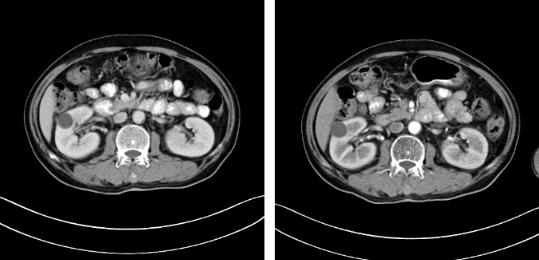

據安圖叔叔的兒子回憶道,安圖叔叔在體檢前沒有發現任何不適的癥狀,在體檢后才知雙腎占位,右腎下級占位16.1*7.2cm,左腎下級腫瘤約3.7*4.3cm的情況。突如其來的病情讓一家人陷入了恐慌,從未想過一個健康自律的人會突然間就被檢出腎癌,還是雙腎。安圖叔叔的兒子激動地說道:“我當時一下子懵了,父親之前表現那么健康,一查竟病得很重,為確診我把父親轉接到新加坡就診,那邊的醫生在看了我父親的片子后都表示這是腫瘤,要做切除雙腎然后再透析,對于我們來說,切腎這樣的治療方案對我們來說是無法接受的,父親畢竟一把年紀,這樣做法太傷他身體。”

2017年9月安圖叔叔開啟新治療之路,入院檢查發現安圖叔叔右腎透明細胞癌T3NxM1IV期、左腎癌、縱隔淋巴結轉移瘤。為緩解安圖叔叔腰疼的狀況,9月21日進行介入治療。經復大專家認真探討后,考慮到安圖叔叔身體精神狀態良好,可進行冷凍消融術。經專家解說和安慰后,安圖一家懸著心終于放下了。

2017年9月29日,從CT影像看到右腎情況更為嚴重。為減緩腫瘤增長的速度,專家進行商議后,最終決定由牛立志教授主刀為安圖叔叔進行了右腎腫瘤冷凍消融術。手術開始后,牛立志教授在CT和超聲引導下,同時使用兩根冷凍針固定病灶,精準滅活腫瘤;術后很成功無不良反應。術后一周進行第二次雙腎腫瘤冷凍消融術。安圖叔叔兒子笑道:“當時真的很緊張,醫生勸慰我無須擔心,都交給他們,我們都很清楚知道父親的病情,真的很感謝也很慶幸我父親遇到復大的醫護人員,免受開刀之痛。住院期間醫護人員很盡心盡力的照顧父親,手術的成功離不開他們的辛勞付出。”